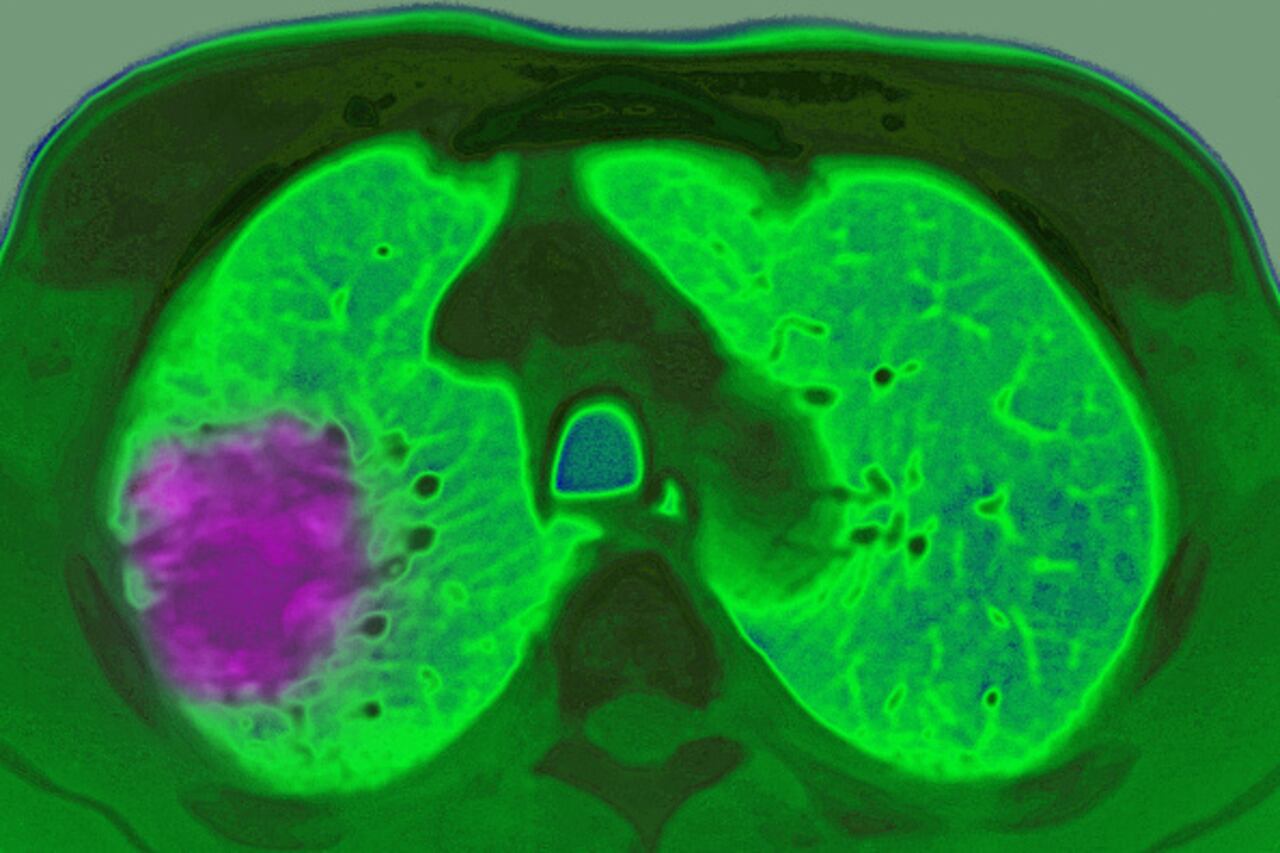

Si los productos que contienen asbesto son alterados, se liberan fibras pequeñas al aire que cuando se inhalan es posible que se acumulen en los pulmones y permanezcan por largos períodos. Con el tiempo pueden provocar inflamación y cicatrización de tejido, lo que es posible que afecte la respiración y cause problemas graves de salud. La exposición al asbesto se relaciona con un mayor riesgo de cáncer de pulmón y mesotelioma, que es un cáncer en las membranas delgadas que recubren el interior del tórax y el abdomen.

Este es un subproducto de la combustión incompleta de materiales orgánicos como madera, aceite combustible, plásticos y desechos de los hogares. El polvo fino de color negro o café puede contener una cantidad de carcinógenos como arsénico, cadmio y cromo. Las personas pueden estar expuestas al hollín por inhalación, ingestión o absorción a través de la piel y es un componente relacionado con mayor riesgo de cáncer de piel, pulmón y esófago.

Este es un elemento natural que se encuentra en la corteza terrestre. Todos los suelos y las rocas, entre ellos el carbón y los fertilizantes minerales, contienen algo de cadmio. Es muy usado para fabricar baterías, pigmentos, revestimientos de metal y plásticos y la exposición al mismo se da en los lugares de trabajo donde se elaboran los mencionados artículos. Las principales rutas de exposición son la inhalación del polvo y los gases y la ingestión accidental de polvo de las manos, cigarrillos o alimentos contaminados. Está relacionado con mayor riesgo de cáncer de pulmón.